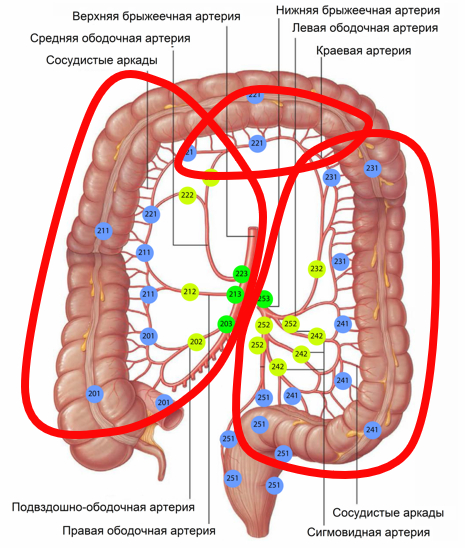

Обычный колоректальный рак растет из полипа. Но не при язвенном колите. Этот же рак, хотя и такой же на микроуровне, растет отовсюду. Язвенный колит поражает всю толстую кишку, соответственно, вся толстая кишка превращается в опухоль. Поэтапно.

Метод хирургического лечения при язвенном колите? Тотальное удаление толстой кишки.

Метод хирургического лечения при колоректальном раке? Удаление части кишки с опухолью и лимфодиссекция (удаление лимфоузлов).

Объединяем, и получаем тотальную колпроктэктомию с комплексной лимфодиссекцией. Операция переходит в категорию "эпичная".

Поэтому пошёл классически, через лапаротомию. В куполе слепой кишки сидела опухоль (к диагностам потом сходил и рассказал в порядке обратной связи). Убраны все лимфоузлы (некоторые до 2 см!), сосуды очищены, D3 лимфодиссекция по всем направлениям. И тонкокишечный резервуар, который был успешно подшит на место. На время его заживления выведена временная стома на пару месяцев. Всё нужное сохранено, всё лишнее удалено.